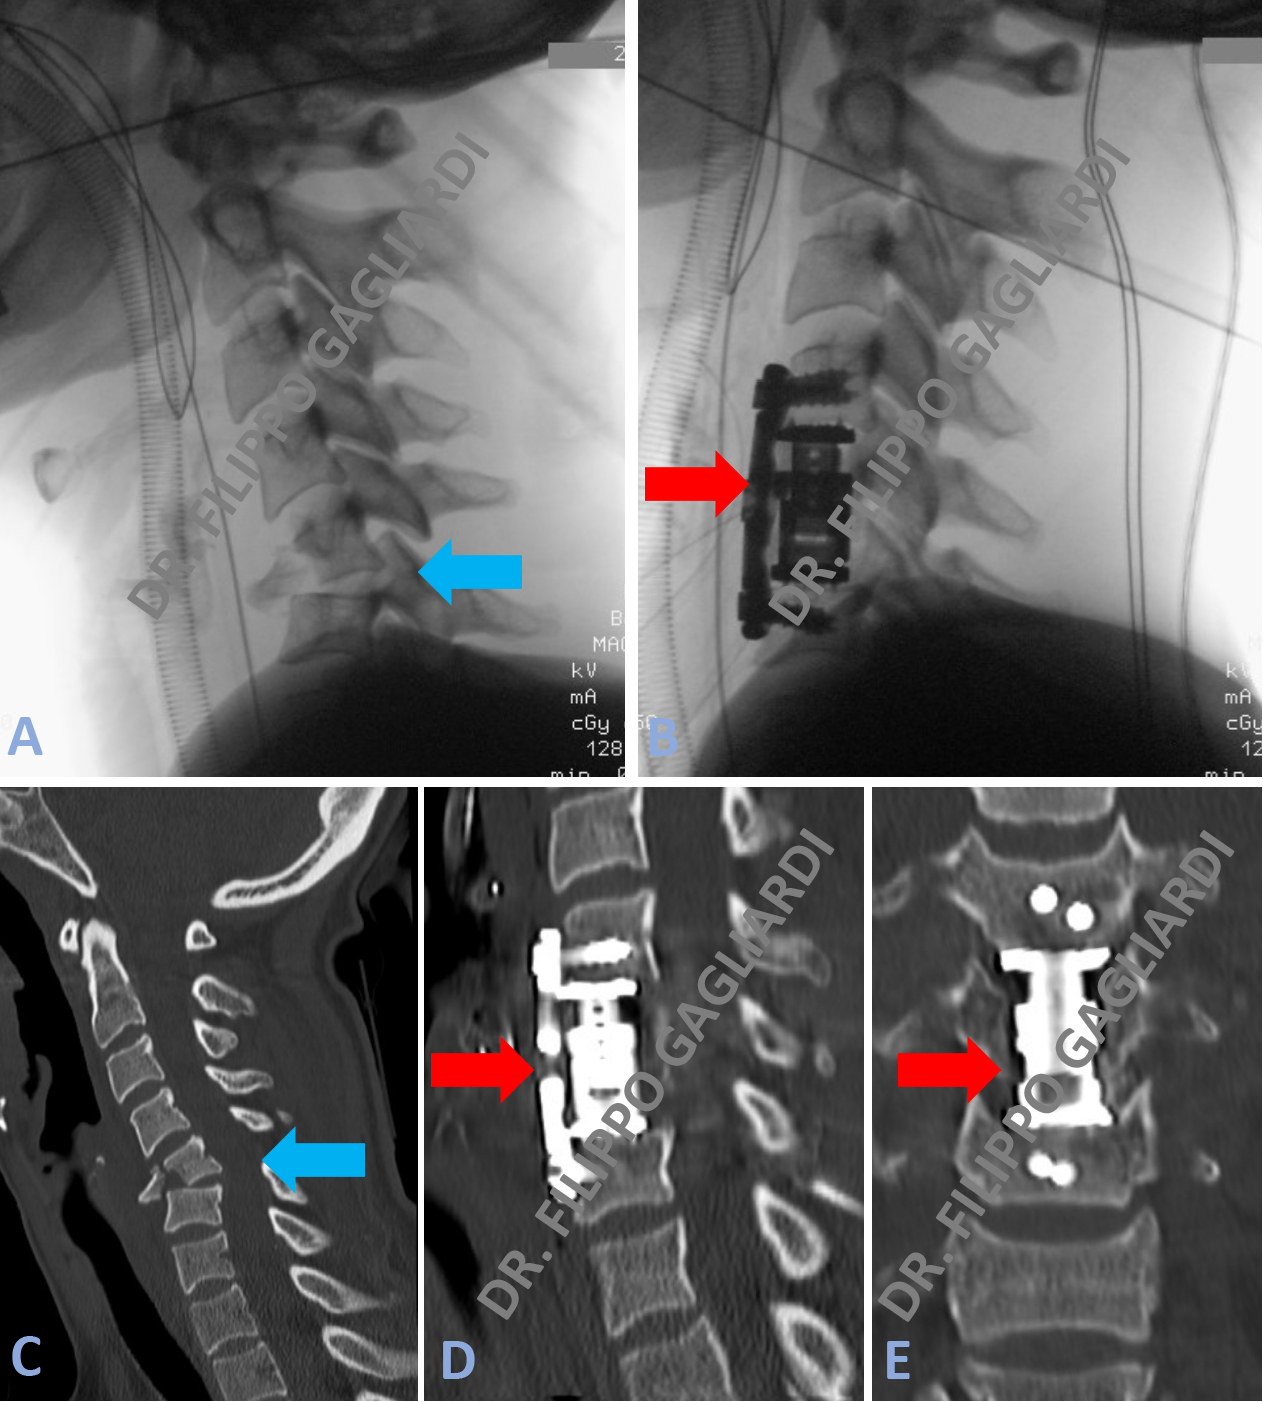

Caso di frattura della quinta vertebra cervicale con scoppio del corpo vertebrale a causa di un incidente della strada. Le frecce azzurre nelle Figure A e C dimostrano lo RX e la TC del collo. Evidente la frattura e la lussazione vertebrale.

Per ricostituire la stabilità vertebrale il Paziente è stato sottoposto ad un intervento in due tempi. La prima fase passando da davanti (tempo anteriore) e poi dietro (tempo posteriore). L'intervento è consistito in una corpectomia (asportazione del corpo vertebrale) della vertebra fratturata. Si è passati, poi, al posizionamento di una protesi espandibile (cage + placca) per via anteriore e viti di stabilizzazione posizionate per via posteriore (frecce rosse Figura B, D, E).

Corpectomia vertebrale cervicale.